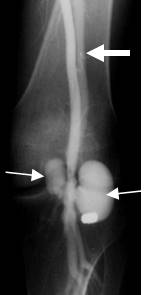

A: Arteriografía AP. Oclusión de la arteria poplítea, después de una luxación de rodilla reducida.

B: Arteriografía lateral. Oclusión de la arteria poplítea, ocasionada por herida con arma de fuego.